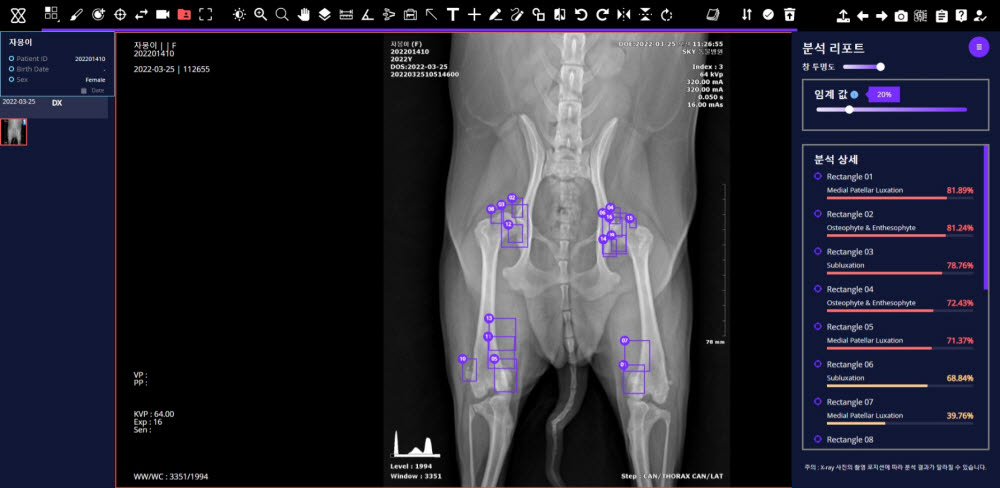

엑스칼리버는 병원에서 촬영한 반려견의 근골격계 질환 7종, 흉부 10종 등 엑스레이 사진을 클라우드에 올리면, AI가 약 30초내 비정상 소견 여부와 위치정보 등 분석결과를 수의사에게 제공하는 웹기반 서비스다.

엑스칼리버 AI의 판독 결과와 국내 대형 동물병원 영상전공 수의사들의 판독 결과를 비교해본 결과, 양측의 의견이 합치하는 비율이 분야별로 84~97%를 기록했다. 진단 보조 솔루션으로 유효성을 입증했다는 의미다.